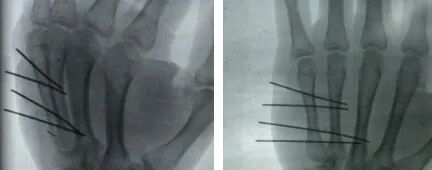

术中,创伤骨科主任马松涛团队在臂丛神经阻滞麻醉下行手法复位闭合,透视下分别于第5掌骨尺侧向桡侧第4掌骨方向打入4枚钛针,术中透视检查复位满意,达到骨折折端不切口,局部不剥离,固定又可靠,术后依从性好,生活又方便恢复又快捷。